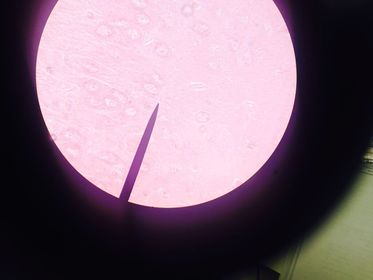

1.- Trichomonas sp 2.- Trofozoito 3.- Núcleo, Membrana ondulante, Cuerpo parabasal

1.- trichomonas vaginalis